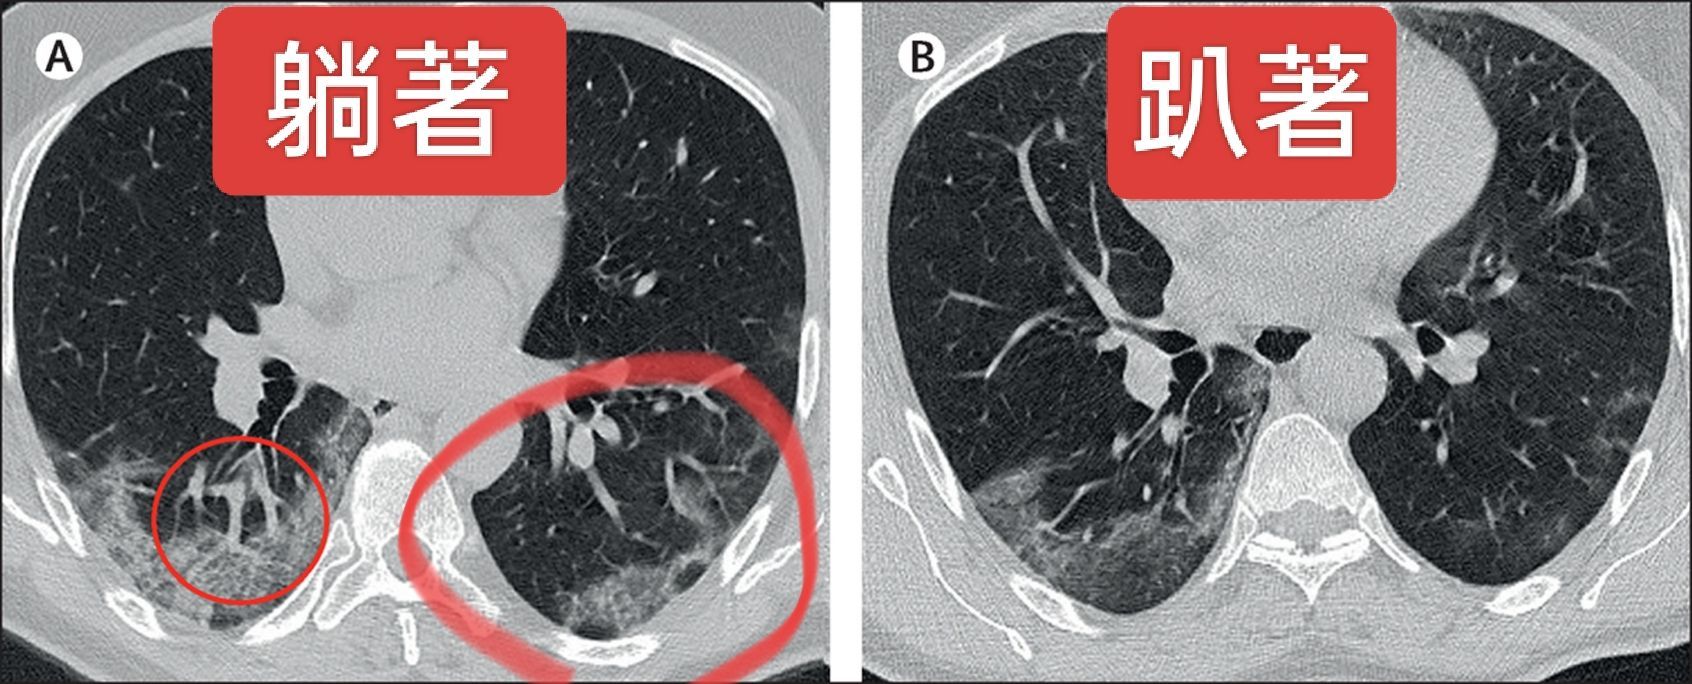

他分享一張刊登在知名醫學期刊《Lancet》的圖片,內容是一名新冠肺炎患者在同一時間躺著和趴著做電腦斷層掃瞄(CT),躺著時可以看到肺炎在心臟的壓迫下明顯更嚴重;至於趴著時可以看到在沒有心臟的壓迫下,兩側肺炎明顯更好,一側的肺炎甚至消失了。

對此,蘇一峰指感冒時本來就有支氣管發炎阻塞的情況下,躺著因為重量的影響,心臟壓在肺上面,加上肺部本身的重量也壓在底層的肺上面,底層的肺要支撐心肺重量下呼吸,會特別辛苦困難,所以只好一直咳嗽把阻塞的氣管咳開,這亦是為何會鼓勵重症肺炎的病人趴睡的原因,以減少肺部的負擔,幫助痰液排除。